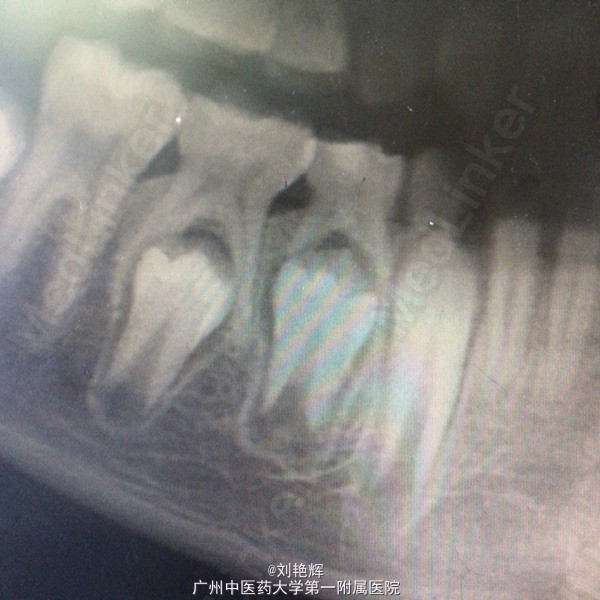

左下乳四合面充填物存,颊侧牙龈略肿胀,冷(-)扣(-) 辅助检查:全景片发现左下乳四根尖阴影,34发育异常

诊断:乳四慢性根尖炎 处理:拔除乳四